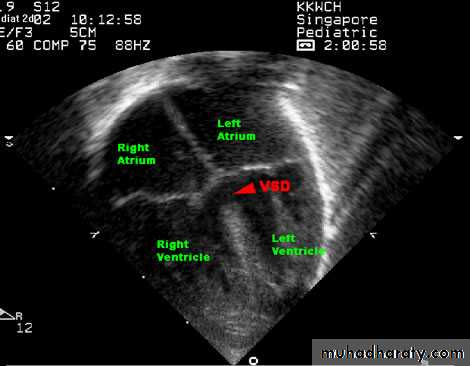

Echocardiography.

Two-dimensional and Doppler echo studies can identify the number, size, and exact location of the defect; estimate PA pressure; identify other associated defects; and estimate the magnitude of the shunt.NATURAL HISTORY